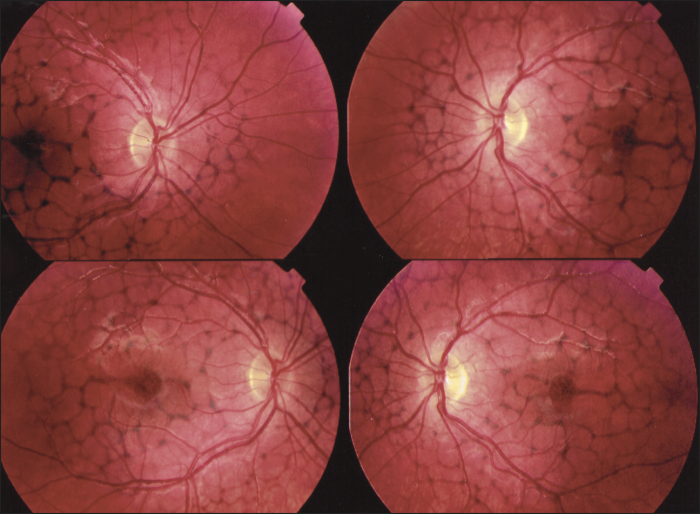

Multifocal pattern dystrophy simulating Stargardt disease

Multifocal pattern dystrophy simulating Stargardt disease is characterized by irregular yellow-white flecks scattered throughout the posterior pole resembling those found in Stargardt disease. The flecks are variable in size, shape and number and are often situated around the retinal vascular arcades, especially nasal and superior to the optic disc as well as in the macular area. Macular abnormalities may range from various patterns of yellow or grayish deposits to well-demarcated lesions of severe chorioretinal atrophy. [16] On fluorescein angiography, the flecks are hyperfluorescent in the early and late phase, sometimes with a central hypofluorescent spot. Important to note is that the characteristic dark choroid seen in Stargardt disease is absent. On fundus autofluorescence imaging, the flecks show increased autofluorescence, often with small adjacent zones of decreased autofluorescence. [16]